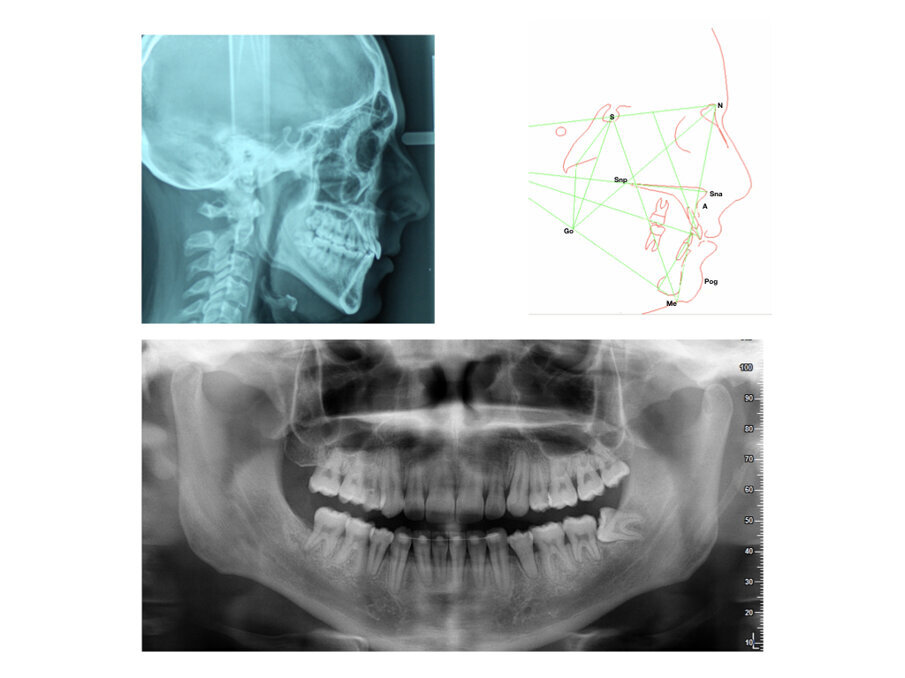

Analisi Radiografica

La radiografia panoramica (Fig. 2) mostra una sovrapposizione dentale sul primo quadrante tra 1.4 e 1.5 e sul terzo quadrante a livello coronale tra 3.4 e 3.5. I condili mandibolari sono simmetrici e non sono visibili patologie mascellari sinusali. Tutti i denti permanenti sono visibili. Vi è l’agenesia del 4.8 ed 1.8 mentre vi è la mancata eruzione del 3.8 ed 1.8. Non vi sono dilacerazioni radicolari, si nota un riassorbimento radicolare con una mancata formazione dell’apice radicolare del 4.5, 3.5. La radiografia laterale del cranio (Fig. 2) mostra le vie aeree superiori libere. L’indice di maturazione delle vertebre cervicali (CVMS) è di grado 6. L’analisi cefalometrica iniziale rivela una classe II sagittale mandibolare a causa di una mandibola retrognatica (SNPog = 72,2°), un tendenza mandibolare di iperdivergenza, ed un angolo interincisale ridotto. L’OJ e l’OB è nella norma.

Sono state utilizzate delle ritenzioni fisse sull’arcata inferiore tramite l’uso di fili di contenzione a livello intercanino. Su l’arcata mascellare è stata utilizzata una ritenzione Hawley rimovibile con indicazione di utilizzo notturno, ogni giorno per i primi sei mesi e successivamente con discontinuità progressiva. L’analisi estetica del viso (Fig. 5) ha mostrato un mantenimento sagittale della proiezione del labbro inferiore. Il paziente ha mantenuto il suo profilo facciale, ciò è causato dalla condizione mandibolare sagittale. Gli affollamenti presenti sono stati risolti, il 2.2 che si presentava con inversione del morso è stato inizialmente esoinclinato e poi, successivamente alla risoluzione dell’inversione del morso, è stato migliorato il torque radicolare. La Classe I bilaterale molare è stata mantenuta mentre è stata risolta tramite l’uso di forze asimmetriche la Classe II canina sx e la Classe III dx (Fig. 5). Dall’analisi radiografica panoramica di fine trattamento si mostra un ottimo parallelismo radicolare, permangono le radici corte su alcuni elementi dentali causate da alterata apicogenesi già presente durante la fase iniziale di trattamento (Fig. 6). La radiografia laterale finale (Fig. 6) mostra come non vi siano modifiche scheletriche evidenti. I rapporti dentoscheletrici nel confronto tra la radiografia latero-laterale iniziale e finale sono stati controllati senza creare una riduzione eccessiva della contrazione d’arcata, portando i valori finali vicino ai valori norma (I/SN 103° - i/GoGn 86°).